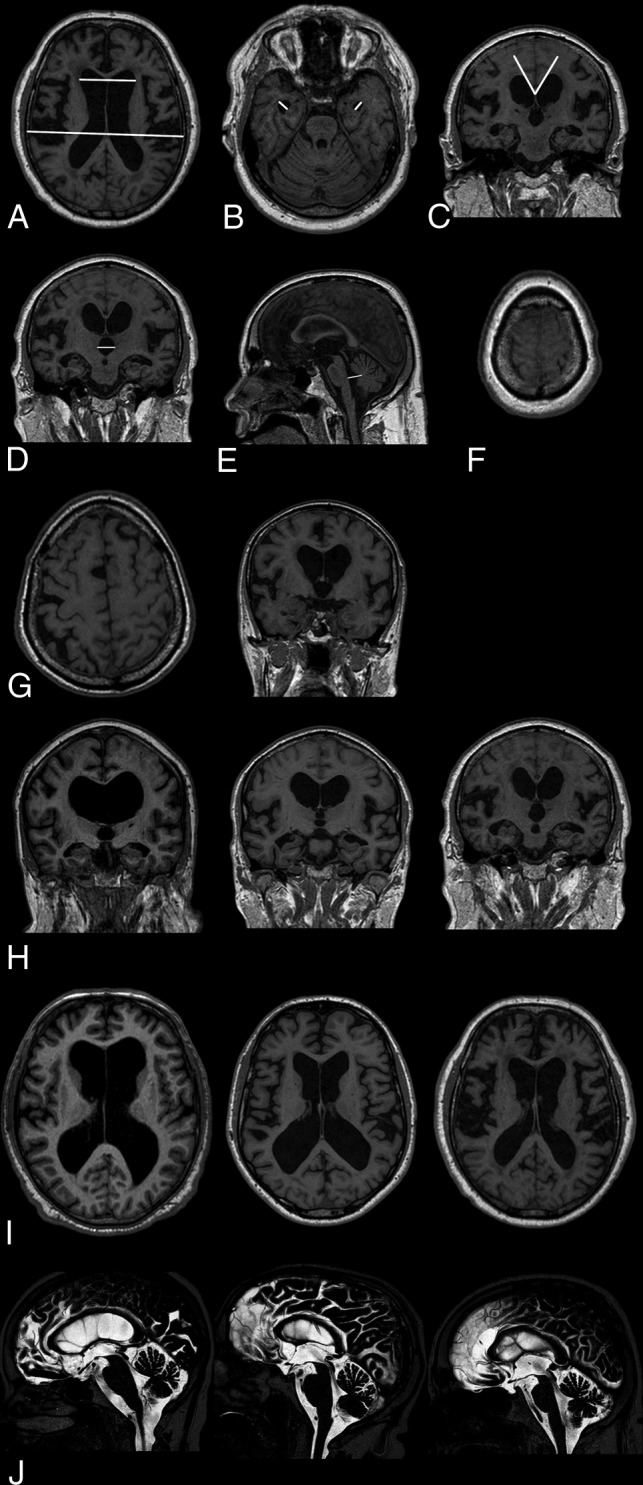

In total, 13 imaging markers were analyzed (Figure).

FIGURE.

Morphologic MR imaging markers analyzed in 168 patients with iNPH preoperatively. A, Evans index. B, Maximum width of the temporal horns. C, Callosal angle. D, Maximum width of the third ventricle. E, Maximum anteroposterior diameter of the fourth ventricle. F, Obliteration of sulci at the vertex. G, Transport of sulci on transaxial and coronal images (left-right). H, Width of the Sylvian fissures graded 0 to 1–2 (left-right). I, Width of the interhemispheric fissure graded 0 to 1–2 (left-right). J, Flow void sign graded 1 to 2–3 (left-right, 0 not shown in the figure).

The EI was measured on transaxial T1-weighted images as the index between the maximum diameter of the frontal horns and the maximum inner skull diameter in the slice above the foramen of Monro (Fig A). Then, the maximum diameter of the temporal horns was recorded bilaterally (Fig B). The callosal angle was analyzed on coronal T1 images at the level of the posterior commissure (Fig C).16

Coronal T1 images were also used to measure the widest diameter of the third ventricle between the anterior and posterior commissures (Fig D). On sagittal T1 slices, the widest anteroposterior midline diameter of the fourth ventricle was determined along a line perpendicular to the posterior border of the brain stem (Fig E).

Obliteration of the high-convexity sulci was assessed on transaxial T1 images and graded as obliterated if no sulci were distinguishable on the 10 most cranial slices covering the vertex (Fig F).

The presence of focally enlarged (transport) sulci was analyzed on transaxial and coronal T1 series. The sulci were only determined as focally widened if there were no signs of general cortical atrophy, the sulcal widening was asymmetric, and the affected sulci lacked connection with the Sylvian fissure. The number of focally widened sulci was recorded (Fig G).

Dilation of the Sylvian fissures was measured on coronal T1 images using an ordinal scale (Fig H).16,22 Widening of the anterior part of the interhemispheric fissure was estimated on transaxial T1 images using a 3-step ordinal scale (Fig I). The flow void phenomenon in the cerebral aqueduct and fourth ventricle (flow void sign) was evaluated and graded using the ordinal scale developed by Algin et al23 and later modified by Virhammar et al (Fig J).8 Periventricular and deep white matter hyperintensities were analyzed on transaxial FLAIR series using the scale developed by Fazekas et al.24

DESH was considered present if patients showed signs of Sylvian fissure dilation (ordinal rating 1 or 2) in conjunction with obliterated sulci at the high convexity.